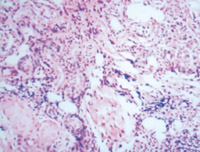

5-2-1 傷后第1天,表皮凝固性壞死,真皮淺層膠原纖維變性  HE×100